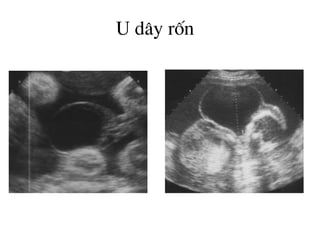

U d©y rèn